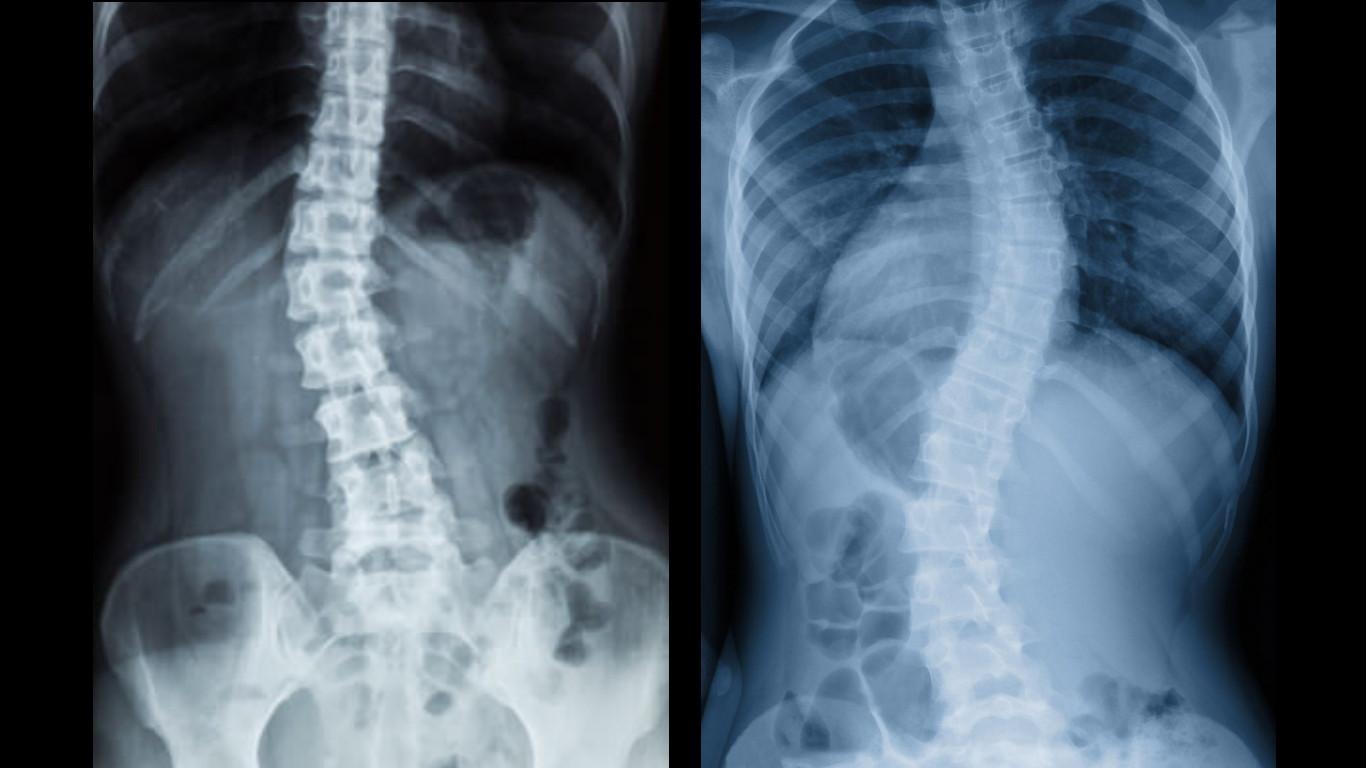

「退化性脊椎側彎」多發生在成年人尤其以年長者居多,由於患者長期來姿勢不良且缺乏適度運動,導致脊椎因承受極大壓力逐漸造成側彎,若角度超過10度以上,就會稱為「脊椎側彎」,往往會有椎間盤突出、神經壓迫、脊椎滑脫等併發症。

亞洲大學附屬醫院脊椎矯正科主任陳衍仁指出,「退化性脊椎側彎」多發生在成年人尤其以年長者居多,由於患者長期來姿勢不良且缺乏適度運動,導致脊椎因承受極大壓力逐漸造成側彎,若角度超過10度以上,就會稱為「脊椎側彎」,往往會有椎間盤突出、神經壓迫、脊椎滑脫等併發症,其中的共同點就是「痛」。